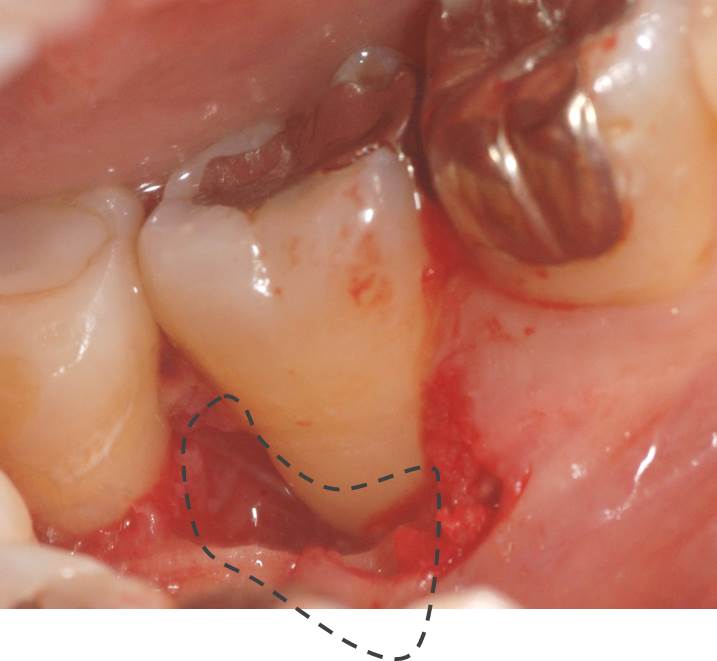

歯周基本治療が終了して、歯周外科手術中の写真です。

点線部分に広くて深い歯槽骨の欠損が認められます。

そこに、自家骨を移植しました。

その後、GTR膜を固定して縫合しました。